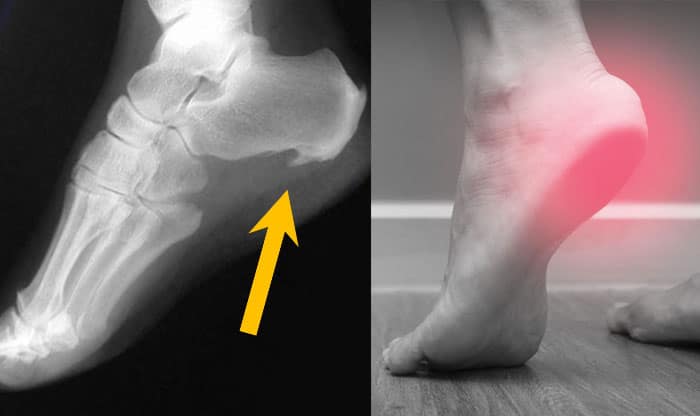

خار پاشنه، یک رشد استخوانی است که در زیر پا ایجاد میشود. علاوه بر این، این عارضه به عنوان «استئوفیت» نیز شناخته میشود. گاهی اوقات ممکن است از زیر پاشنه تا قوس پا گسترش پیدا کند که به این ناحیه «فاسیای کف پا» گفته میشود. زمانی که خار پاشنه در اشعه ایکس دیده میشود، ممکن است تا یک و نیم سانت طول داشته باشد.

زمانی که بیمار با چنین علائمی به پزشک مراجعه میکند، جهت تشخیص علت، از پای او عکسبرداری میشود. مشاهده برجستگی در اشعه ایکس تنها راهی است که میتوان این عارضه را تشخیص داد. به این نکته توجه داشته باشید تمام افرادی که خار پاشنه دارند، لزوما به این معنی نیست که تمامی این علائم را تجربه میکنند. گاهی فردی ممکن است دچار خار پاشنه باشد، اما هیچ علائمی را احساس نکند.